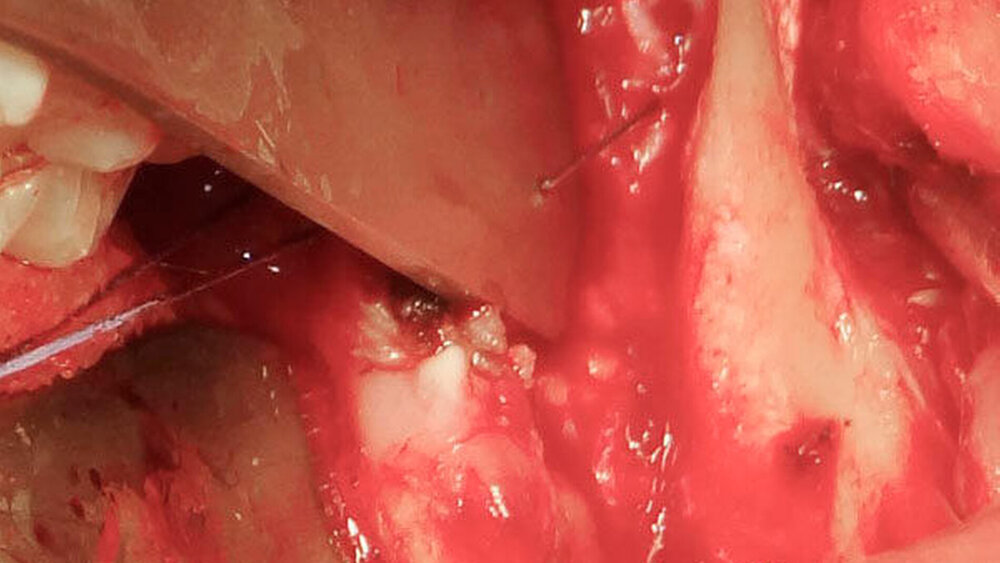

Wir berichten über den Fall eines 29-jährigen Patienten, welcher notfallmäßig vom niedergelassenen MKG-Chirurgen nach einer Weisheitszahn-Osteotomie regio 28 und 38 in unsere Klinik überwiesen wurde. Im Rahmen des ambulanten Eingriffs in lokaler Anästhesie wurde eine Leitungsanästhesie im Bereich des Nervus (N.) alveolaris inferior links vorgenommen. Nach erfolgreicher Osteotomie des linken unteren Weisheitszahns imponierte in der postoperativen Röntgenkontrolle (Orthopantomogramm) ein circa 2,5 cm langer metallischer Fremdkörper im Bereich des aufsteigenden Unterkieferastes links (Abbildung 1).

Als klinisches Korrelat erwies sich die bis dahin nicht vermisste Dentalkanüle der verwendeten Karpulenspritze. Auf dringende Empfehlung des behandelnden Kollegen erschien der Patient nach dem Eingriff postwendend in unserer Klinik. Hier wurde dann die sofortige Entfernung der Kanüle im Rahmen einer Notfall-Operation veranlasst. Zur Detektion der Kanüle wurde präoperativ eine dreidimensionale Bildgebung im Sinne einer Computertomographie (CT) veranlasst.